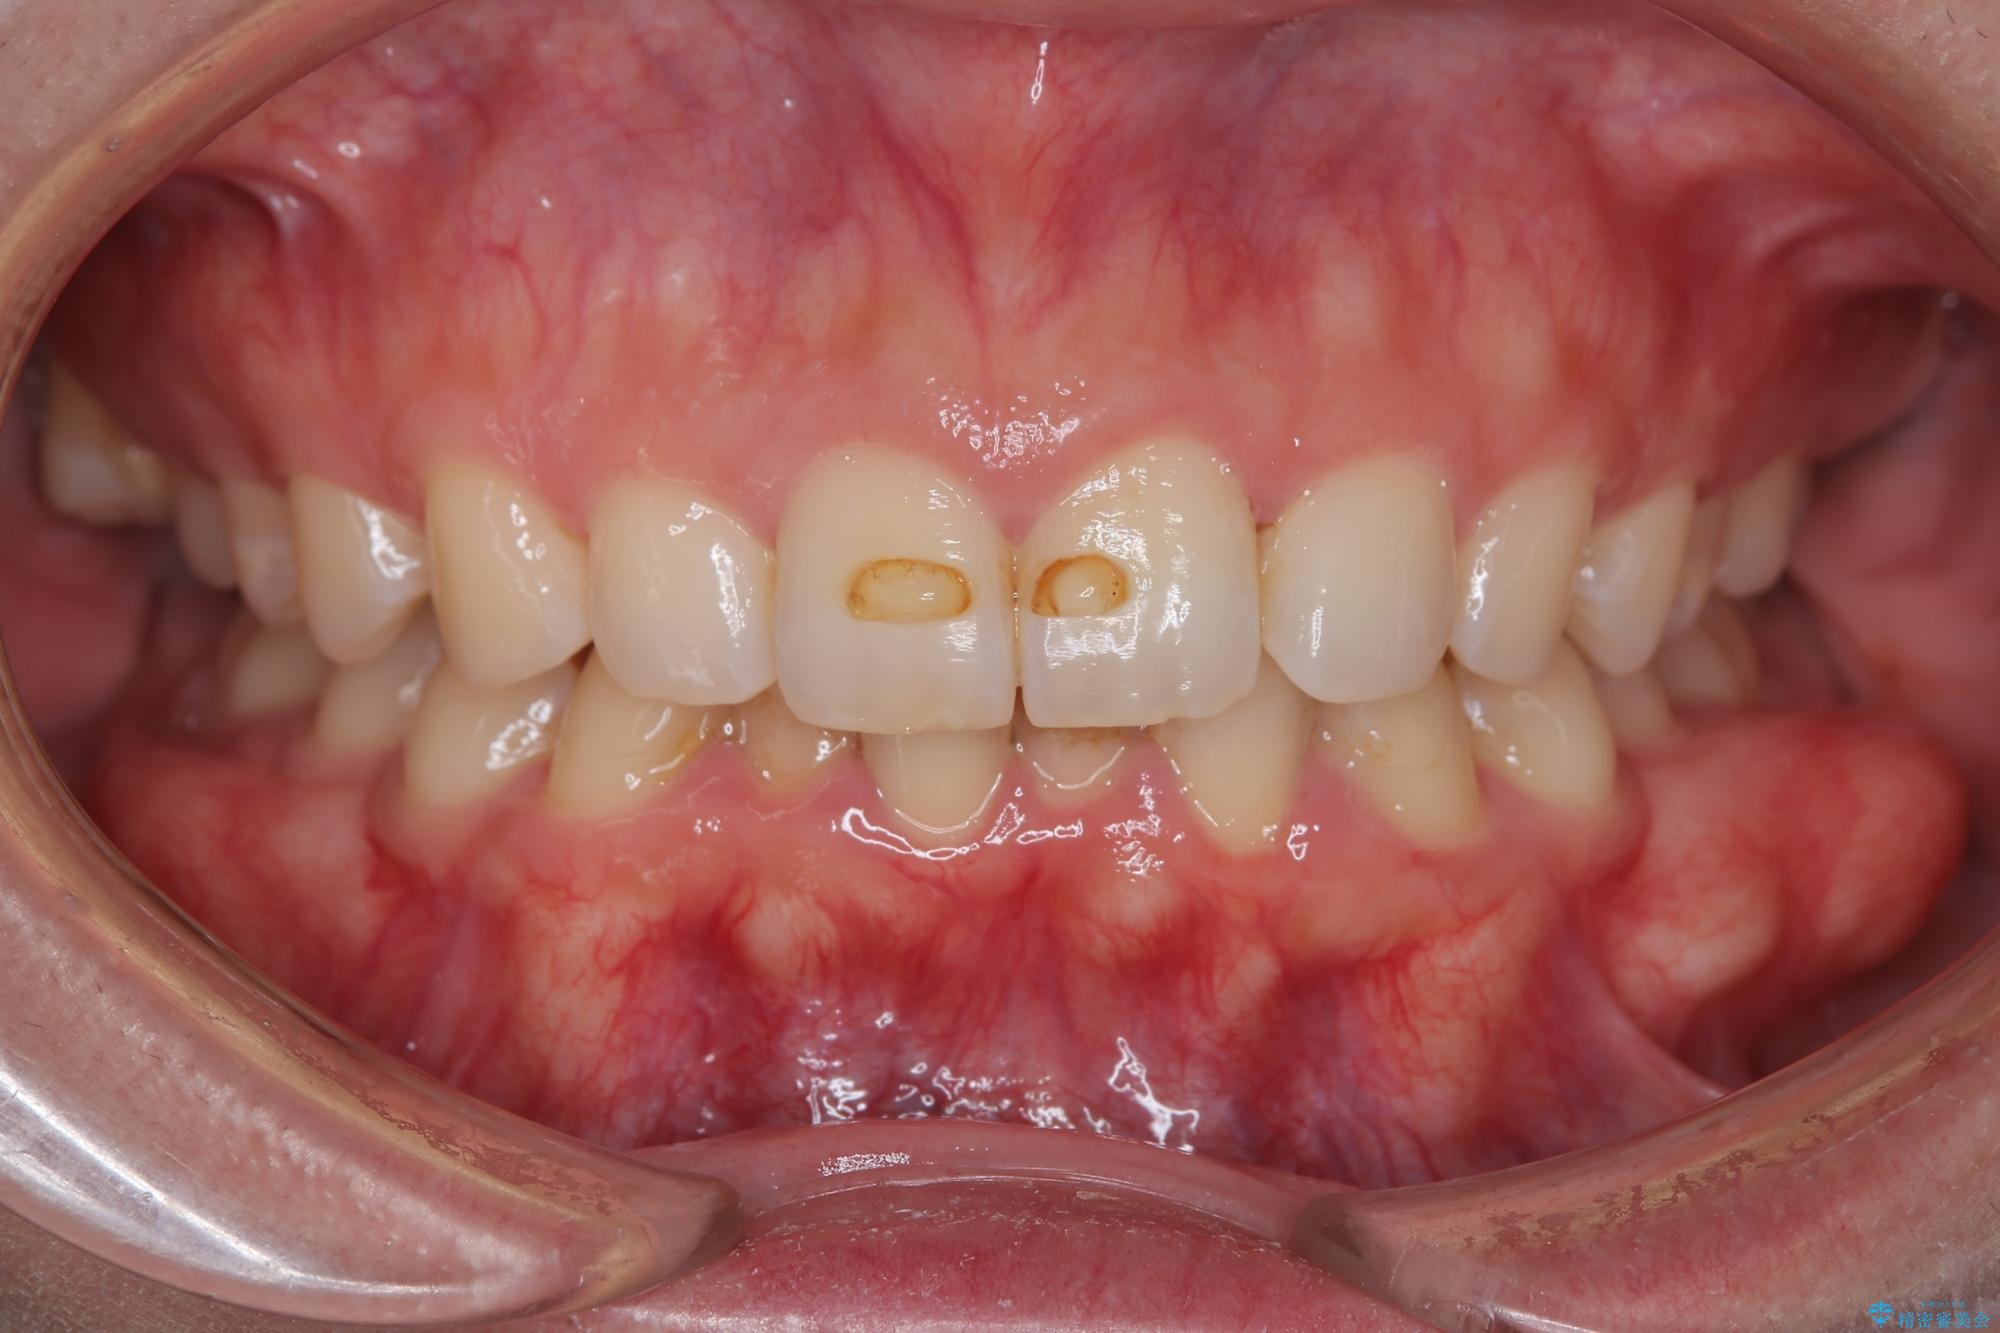

- 下の歯のがたつきを主訴に来院されました。

下の歯のがたつきと右の奥歯の噛みあわせ改善するために治療計画を立てることにしました。

下の前歯のがたつき改善にはIPR(歯と歯の間を削る処置)を行いました。

ゴム掛けを頑張っていただいたので、噛みあわせも改善され綺麗な歯並びになりました。